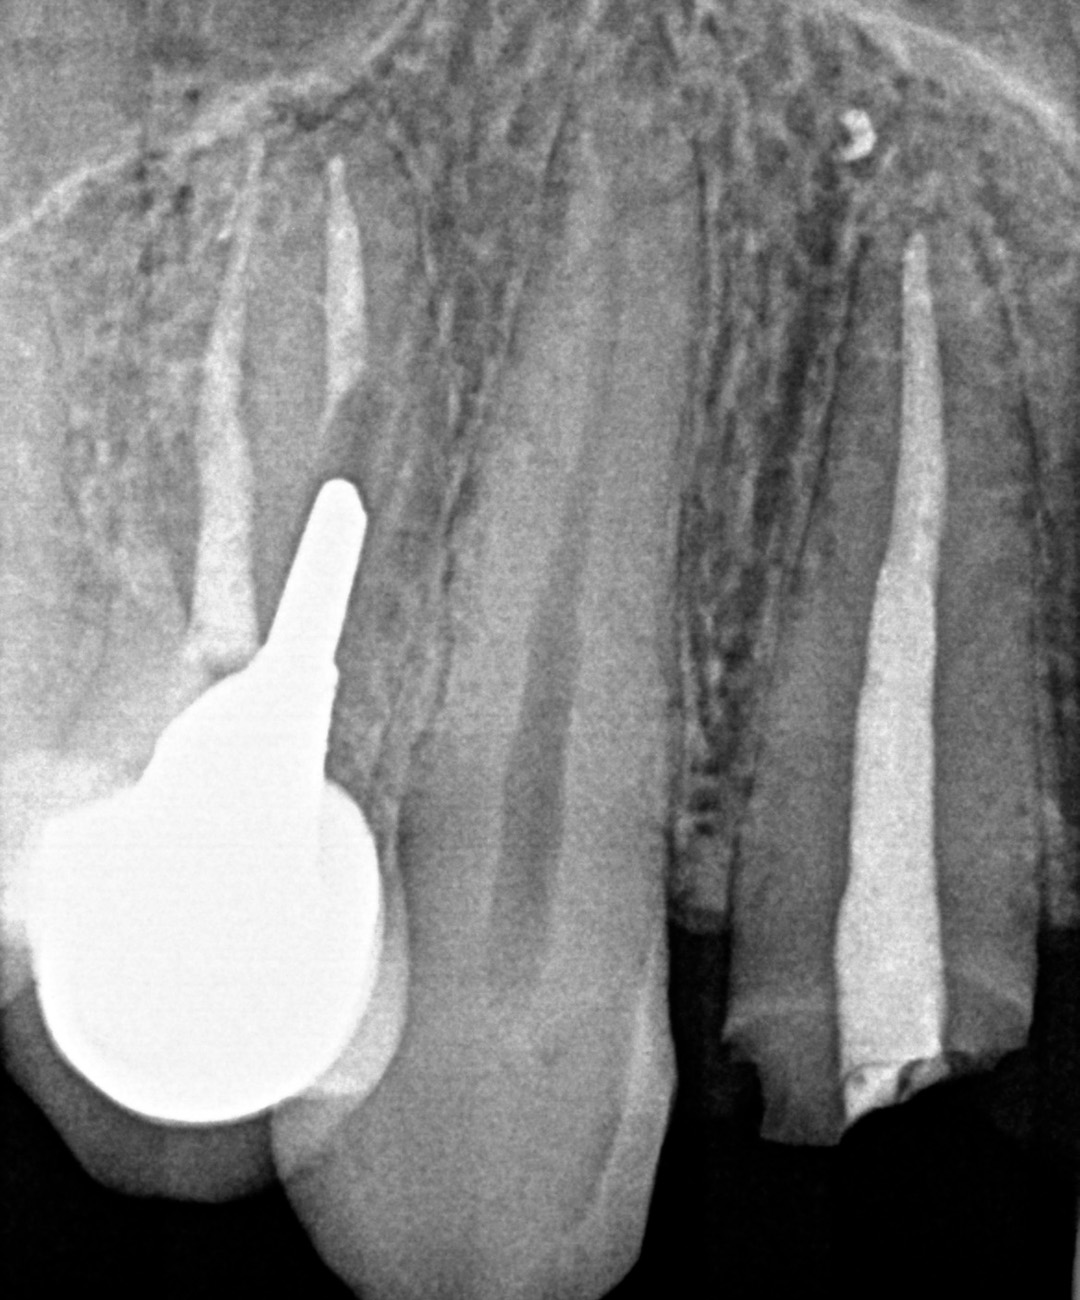

Four months post-placement, the implant site exhibited stable soft tissue contours and full graft integration. A screw-retained lithium disilicate crown was delivered and bonded to a customised anodised titanium abutment. Radiographs confirmed excellent osseointegration and bone preservation. Post-operative care included chlorhexidine 0.12% gel application twice daily for 14 days. The patient expressed high satisfaction with the aesthetic result, and no recession or tissue shrinkage was observed during the healing period.

An intraoral scan and a CBCT image were acquired as part of the comprehensive assessment. The images were matched using dental Blue Sky Bio software to facilitate the design of the surgical guide, using a prosthetically-driven planning approach to find the ideal 3D position of the implant. The surgical template was 3D printed and sterilised in preparation for surgery.

Surgery and initial outcomes